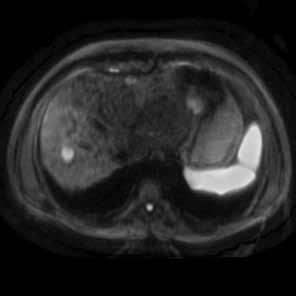

T2脂肪抑制图像,清晰显示肝实质内存在大量环状低信号改变,这是肝硬化所导致的硬化结节的典型表现;同时还可见两类圆形高信号病灶

弥散图像显示相应病变呈高信号

影像分析: 平扫T2图像:充分显示了磁共振在软组织对比分辨率上的优势,更敏感的显示肝硬化所导致的硬化结节。当硬化结节发展演变为癌前病变及肝细胞肝癌时,因为动脉供血增多、肝血窦容积增大以及肿瘤血管增多等改变,导致病灶内血容量增多,血流速度缓慢,从而导致T2弛豫时间延长,因而这类病变在T2相可以表现为高信号改变。 弥散成像:可以敏感检测到病灶内水分子扩散异常,能更敏感的发现小肝癌病变。 LAVA Flex 多期动态增强:病灶在动脉期强化,提示病变以动脉供血为主,这是肝硬化再生结节向不典型增生结节及肝细胞肝癌转变过程中的一个重要病理改变;而静脉期及延迟期病灶强化消退提示相应病灶门脉供血减少,这实际上是鉴别高度不典型增生结节(High Grade Dysplastic Nodule, HGDN)和肝细胞肝癌另一个重要依据。